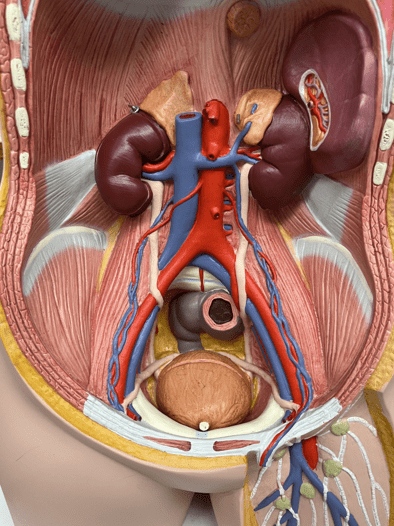

7

New cards

tunica media

• The middle layer of an artery wall.

• The smooth muscle allows for vasoconstriction and vasodilation.